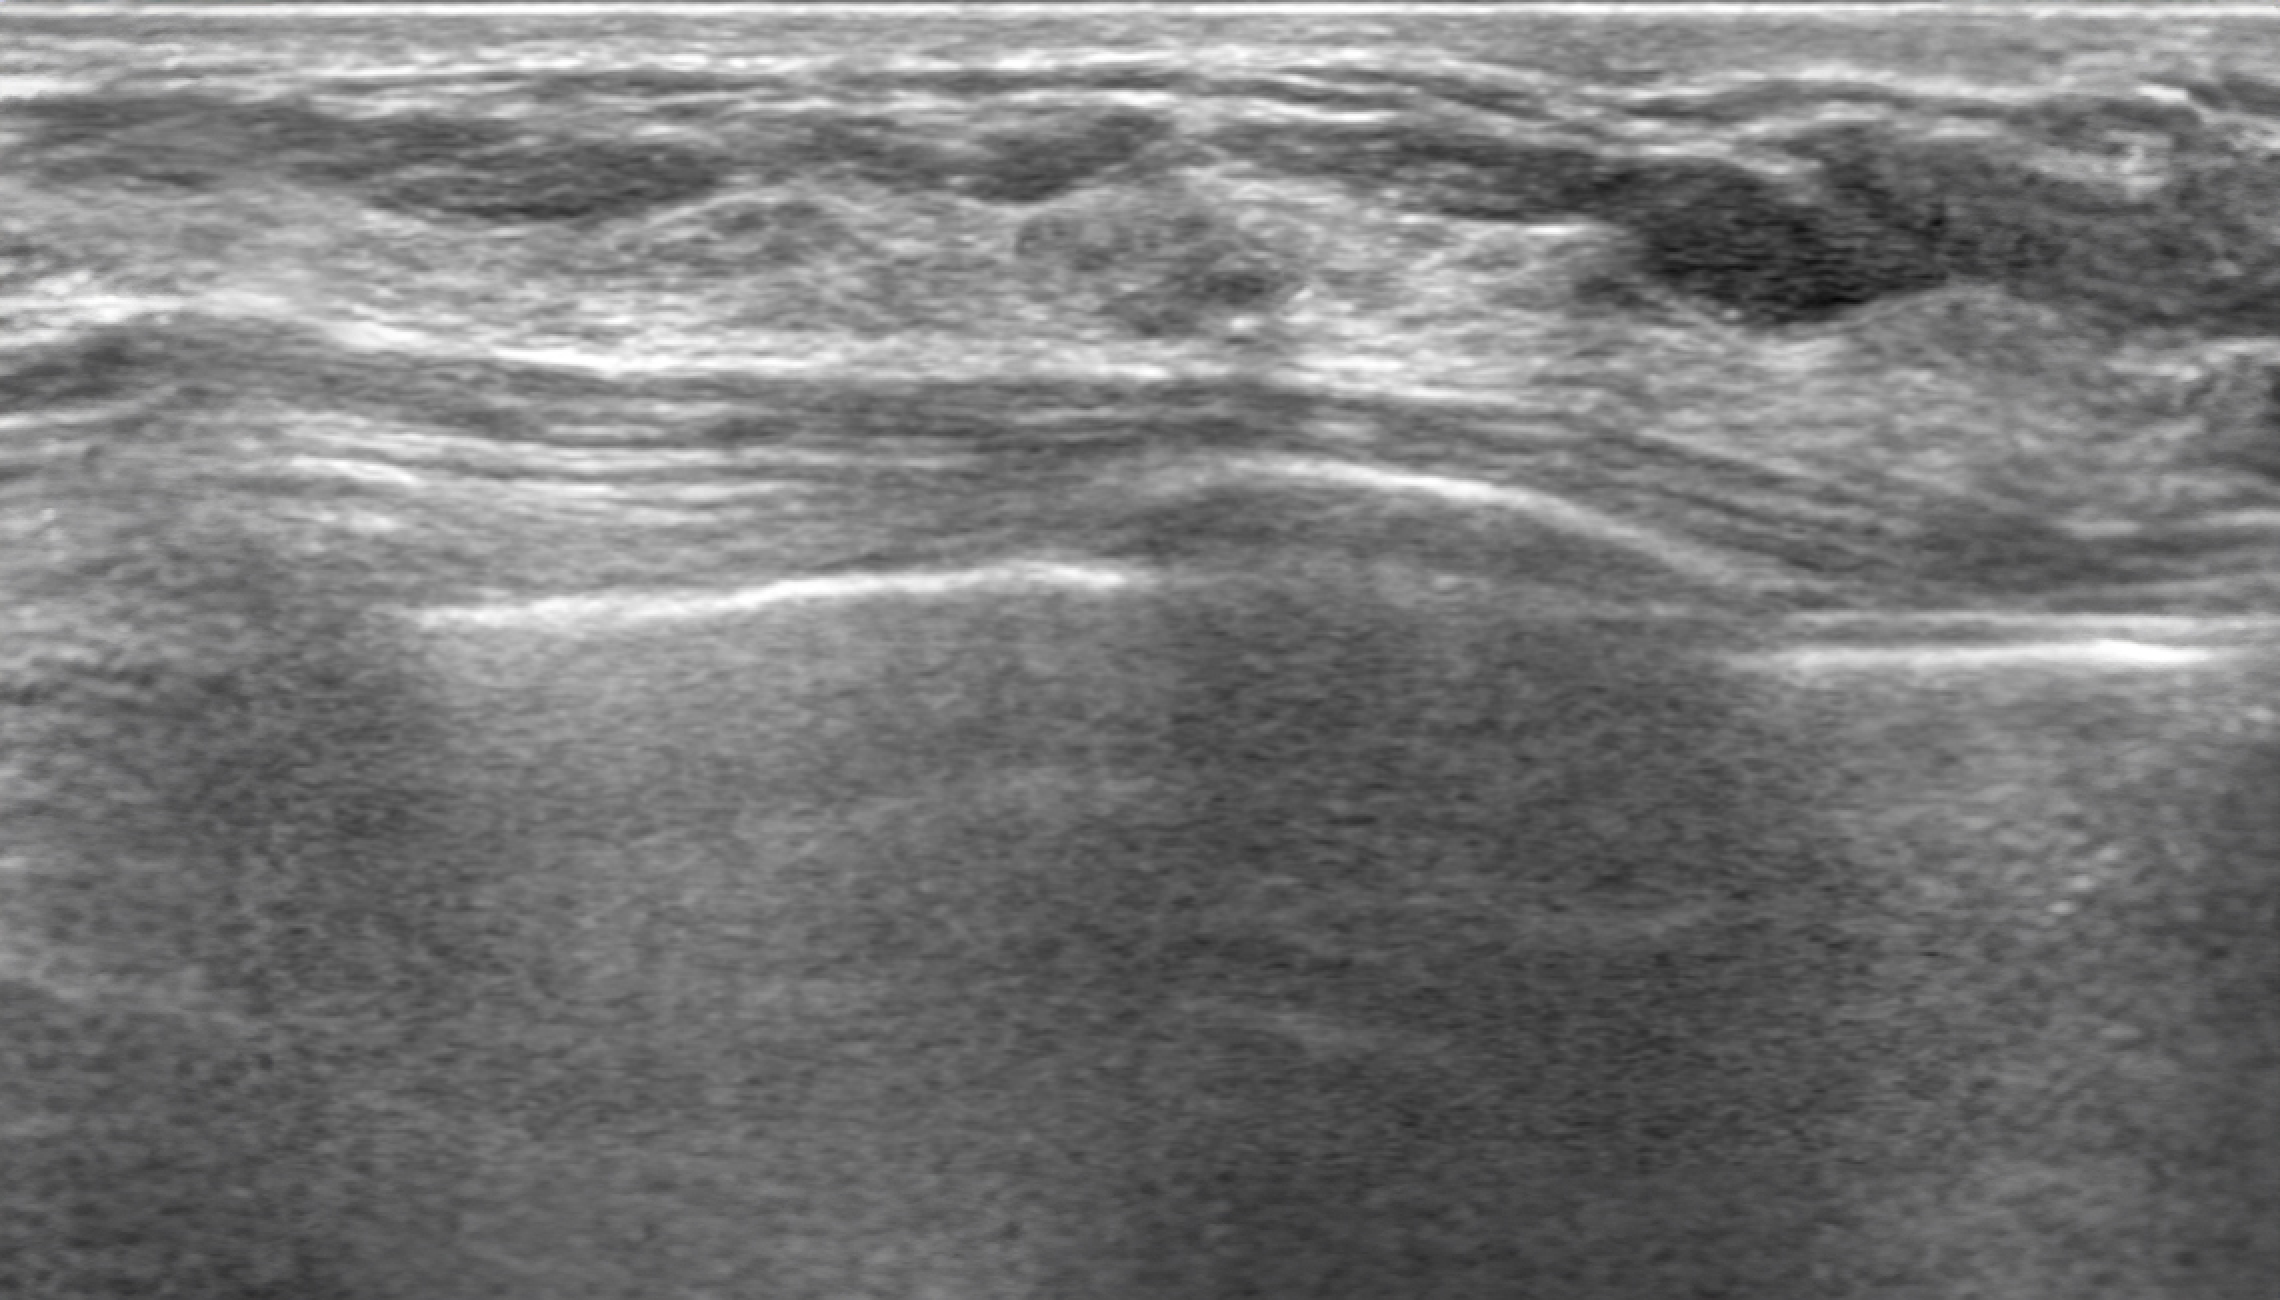

Automatic Detection of Abnormal Lesions

Automatically detects the locations of abnormal lesions in breast ultrasound images in real time.